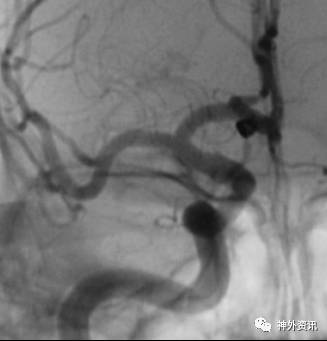

病例一

病例二

病例三

病例四

病例五

病例六

病例七